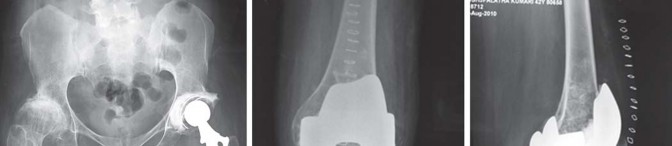

يميل مرضى التهاب المفاصل الروماتويدي اليفعي إلى امتلاك قناة نخاعية فخذية ضيقة جدًا مع عدم توافق بين قطر القناة القريبة والبعيدة. يمكن أن يختلف التجويف الحقي من النوع المشوه (كما يظهر في الشكل 29.1) إلى النوع المنغمس (كما يظهر في الشكل 29.2) أو قد يكون مفصل ورك ملتحم (كما يظهر في الشكل 29.3).

نمط انغماس الورك